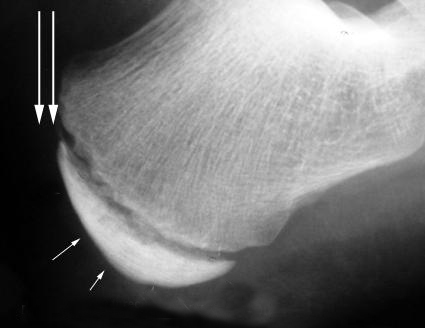

La apófisis calcánea es una inflamación aguda del cartílago por el desarrollo del talón. Durante el periodo de crecimiento se genera tensión muscular en el Tendón de Aquiles y la fascia del pie.

Al tratarse de una patología provocada por la tracción excesiva y repetida del Tendón de Aquiles y fascia plantar, el tratamiento irá encaminado a disminuir esa tensión.